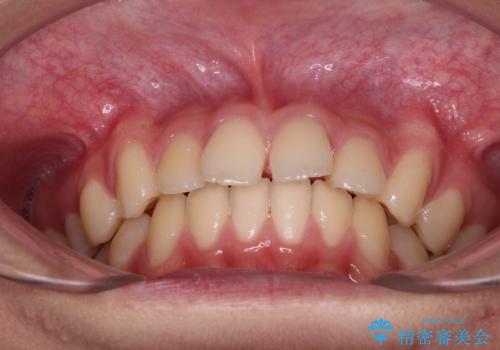

- 前歯のデコボコと隙間を気にして来院された高校生の患者様です。

下顎前歯が上顎前歯を突き上げるような咬み合わせとなっており、その影響で上顎正中に隙間ができている状態でした。

叢生の程度は軽度であり、本人もしっかりと使用する自信があるとのことだったので、インビザラインによる矯正治療を行うこととしました。